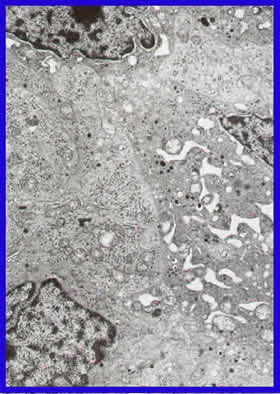

Microscopía Electrónica

Células tumorales poligonales, núcleo central y cromatina dispersa y nucleolo. La densidad citoplásmica uniforme con complejos de organelas parecidas al de las glándulas neuroendocrinas. Mitocondrias y cuerpos de Golgi numerosos.

El pigmento intracelular observado con microscopio de luz, se muestra aquí denso, amorfos, y material de membrana citoplásmica de consistente apariencia de lipofuscina.

30.000x